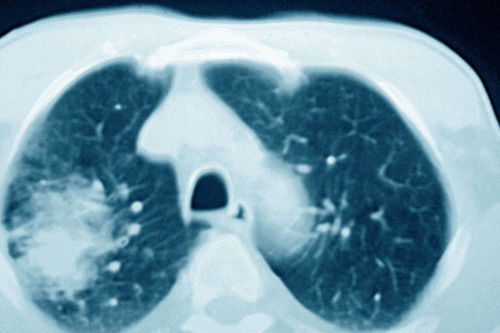

东北地区(黑龙江、辽宁、吉林):肺癌的发病率全国最高,工业污染和吸烟率超过50%,成为双重的主因。